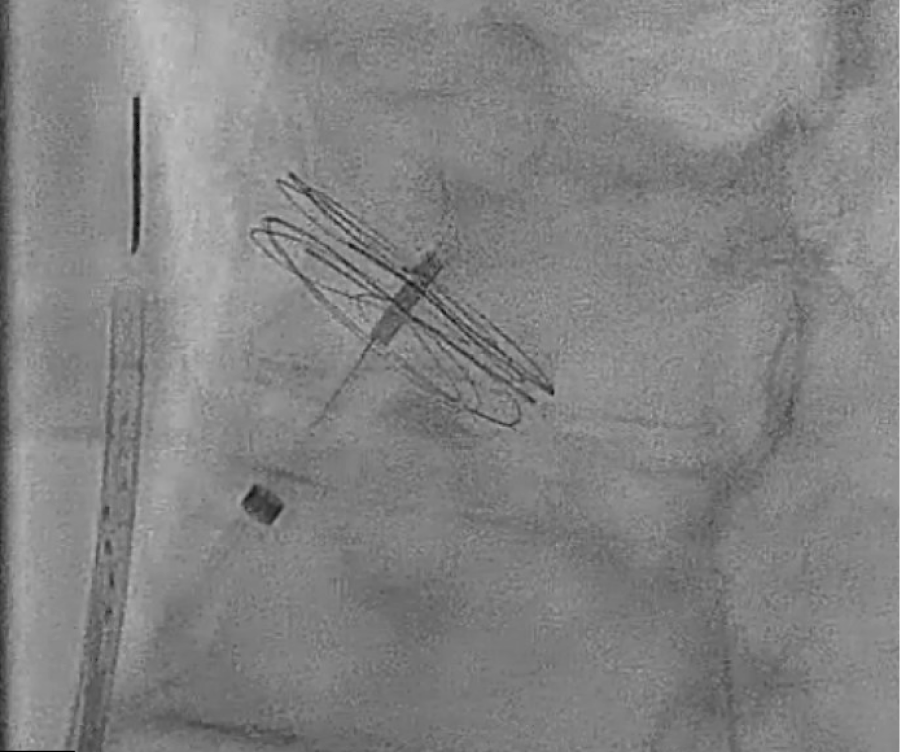

The patient’s clinical condition was consistent with Platypnea-Orthodeoxia syndrome based on the findings described above. A transthoracic echocardiogram indicated an ejection fraction (EF) of 51-55%, with mild left ventricular hypertrophy (LVH) and mild right ventricular dilatation. The bubble study was inconclusive. A transesophageal echocardiogram (TEE) revealed that the interatrial septum was aneurysmal, and a large PFO was visible on color Doppler imaging and following the injection of agitated saline contrast, as shown in figures 1 and 2. The patient underwent transcatheter closure of a patent foramen ovale using a 30 mm Gore Cardioform device, as depicted in figure 3 and 4. Immediately after the procedure, a repeat bubble study was conducted, which showed no bubbles crossing the patent foramen ovale (PFO). He was placed on dual antiplatelet therapy, with aspirin and clopidogrel for one month, followed by aspirin indefinitely. On the day of discharge, the patient was sitting upright in bed with oxygen saturation levels at 94% on room air and reported no shortness of breath. The patient was feeling much improved. The patient's care in the hospital involved a multidisciplinary approach that included teams from cardiology, pulmonology, and hospital medicine. Following hospital discharge, the patient had follow-up appointments in both the cardiology and pulmonary clinics and underwent a transthoracic echocardiogram (TTE) one month after the procedure. The left atrial cavity is moderately dilated. No patent foramen ovale was detected during the agitated saline injection. The patient did not report any breathing issues, and his oxygen saturation on the day of the follow-up was 94%.

Figure 3: Gore placement with intracardiac echo (ICE) guidance. View Figure 3